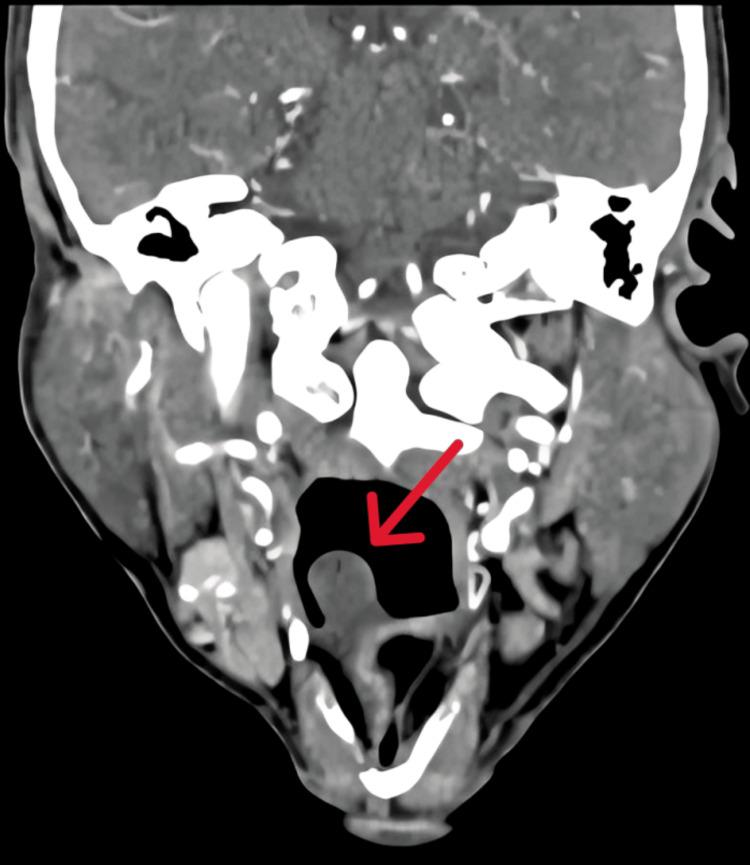

Vallecular cysts (VCs) are rare benign lesions arising from the obstruction of mucous gland ducts. VCs are uncommon anomalies found in both pediatric and adult populations. They are also known as mucous-retention cysts, preepiglottic cysts, ductal cysts, base-of-tongue cysts, and epiglottis cysts. VCs are often asymptomatic in adults and may present with nonspecific symptoms such as globus sensation, voice changes, dysphagia, hoarseness, or airway obstruction when symptomatic. This case report details a rare occurrence of a giant VC in an adult male, emphasizing the diagnostic approach and surgical management and highlighting the importance of managing the airway in such cases and the advantages of endoscopic procedures.

会厌谷囊肿(VCs)是由黏液腺管阻塞引起的罕见良性病变。VCs在儿童和成人中均为不常见的异常情况。它们也被称为黏液潴留囊肿、会厌前囊肿、导管囊肿、舌根囊肿和声门上囊肿。VCs在成人中通常无症状,有症状时可能表现为咽部异物感、声音改变、吞咽困难、声音嘶哑或气道梗阻等非特异性症状。本病例报告详细介绍了一名成年男性罕见的巨大VCs病例,强调了诊断方法和手术管理,并突出了在此类病例中气道管理的重要性以及内镜手术的优势。